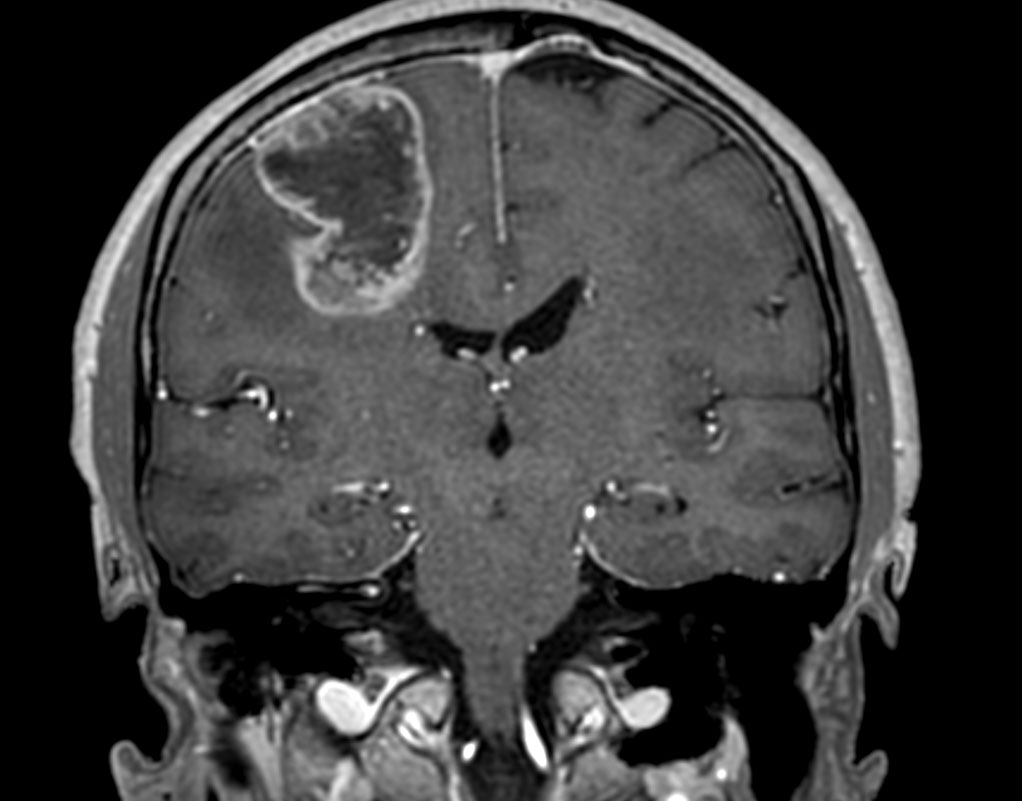

3D T1w TFE (coronal reformat)

-

3D T1w TFE with gado (coronal reformat)